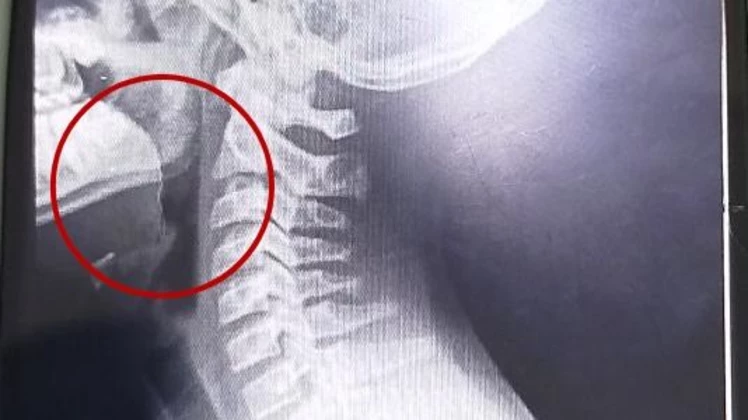

Una vez en el hospital, la situación tomó otro rumbo. Los médicos detectaron lesiones en la garganta y resolvieron su internación inmediata. Se realizaron estudios para descartar infecciones, cuyos resultados fueron negativos, pero la clave apareció con las imágenes: detectaron un objeto extraño alojado en la vía aérea superior.

Allí se produjo el hallazgo más impactante: un alambre fino estaba incrustado en su garganta. El elemento, que habría estado dentro de la galletita consumida, no había sido visible en la primera revisión.

La intervención se realizó mediante una laringoscopía, que resultó exitosa y sin complicaciones. Luego de una evolución favorable, el adolescente recibió el alta médica y se recupera en su domicilio.